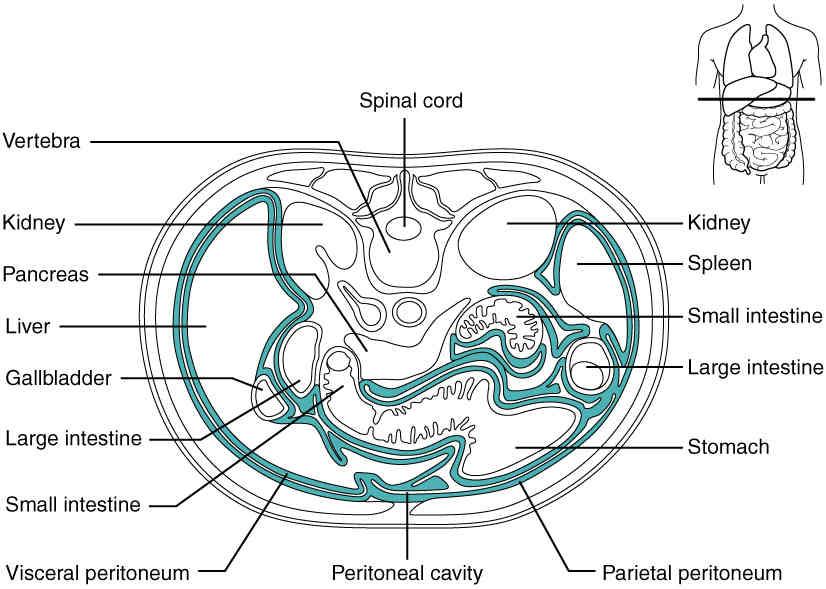

This page is under construction. For now, it is just a resource of the images found in the OpenStax Anatomy and Physiology Handbook. It wil slowly change into a revision tool. Each slide has a number. Use this to refer to the slide. When completed, it will have an unlabelled section, with labelled slides in parallel. On the unlabelled slides, write your answer and use the labelled slide to assess yourself. Keep track by also noting the number on each slide. Improvement at each attempt is important, more so than full marks on a first attempt.